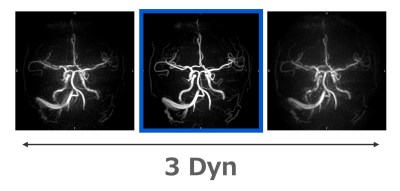

Super rapid PCA was constructed by combing a transverse acquisition, optimization of voxel size, shortest repetition time (TR), and parallel imaging. Tilted optimized non-saturating excitation (TONE) enhanced the depiction of the distal arteries. We investigated the optimal setting of TONE and image quality in the volunteer study. The coefficient of variation of signal intensity and signal behavior of cerebral vessels were evaluated. The visual evaluation also was performed by comparing conventional time-of-flight MRA images. As a clinical study, we obtain both MRA and black blood (BB) images in 36 AIS patients. BB images were demonstrated as a subtraction image between an MRA image and from magnitude image. We named this technique DEPICT (DEpicting blood clot and MRA using Phase contrast angiography with Image Calculation for Thrombectomy) We compared the reliability of the clot location using AC1 in BB image with susceptibility vessel sign (SVS) in T2*WI.5,6) We assessed the robustness of motion artifacts through visual evaluation. Additionally, we attempted a dynamic study consisting of over three times PCA with 45 seconds for strong motion patients with stroke. We used images without motion artifacts to assess cerebral arteries.

Super rapid PCA provided diagnosable image quality. Especially, main arteries were depicted with superior quality and within a shorter scan time compared to a conventional TOF MRA. This is a large advantage for AIS management. The clot location providing a BB image contributes to the strategy of mechanical thrombectomy. Hence, DEPICT will work as a first-choice technique to assess acute ischemic stroke. Dynamic scan of super rapid PCA showed the potential to overcome strong motion artifacts of patients with stroke.

The concept of dynamic study to overcome motion artifacts.